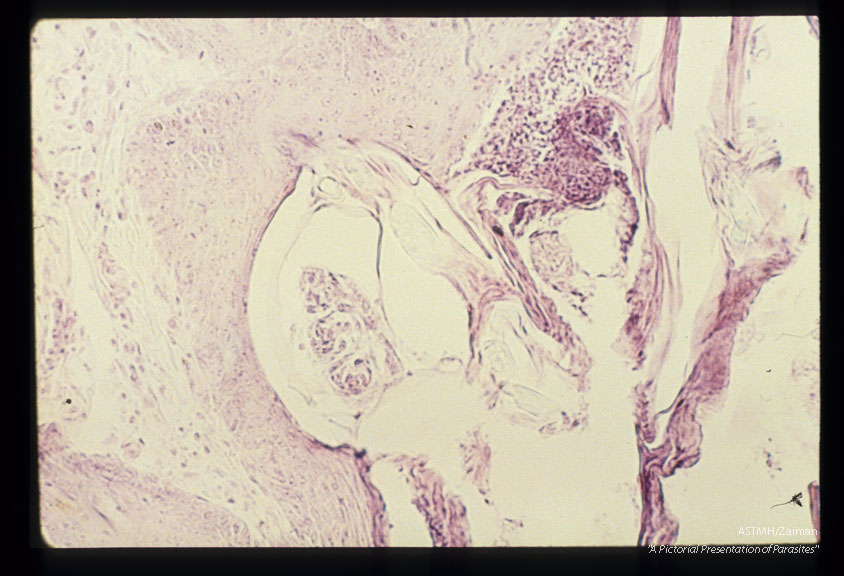

Section through skin showing burrowing mite.

Sarcoptes scabiei

Description: Section through skin showing burrowing mite.